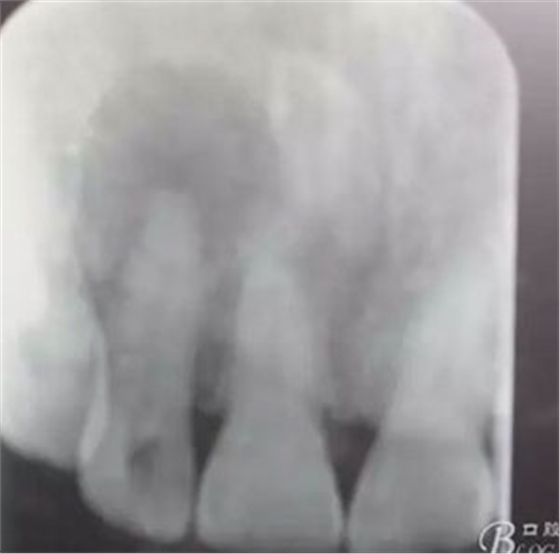

圖1.患者在根管術(shù)前的根尖片影像檢查:12有開髓孔,根尖有橢圓形陰影。